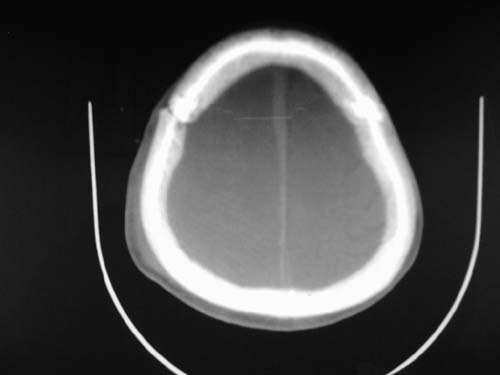

标题: CT17020:是硬膜下的吗?

脑中线内血肿,是硬膜下的吗?

脑中线内血肿——硬膜下血肿。

脑中线内血肿——硬膜下血肿。我们一般认为中线即可是硬膜下,也可是蛛网膜下腔的。边缘锐利,张力高的考虑硬膜下的,边缘模糊的,考虑下腔的。如果有老师有肯定的答案,麻烦下给我发个短信

硬膜下血肿,有颅骨骨折

支持镰旁硬膜下血肿,颅骨骨折,头皮损伤.

这个病人年龄不小吧,右侧脑沟不清,中线结构稍有左移,右侧额颞顶及右镰旁硬膜下血肿,另有蛛血,骨折。

外伤后引起的颅骨骨折、硬膜下血肿、皮下血肿,颅骨骨折引起的矢状窦破裂,形成大脑纵裂内血肿。